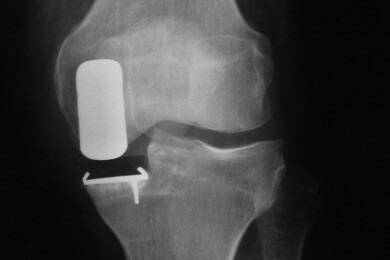

Eines der bekanntesten Symptome der Arthrose sind die damit einhergehenden Gelenkschmerzen, Entzündungen und Schwellungen. Betroffen vom Gelenkverschleiß sind vor allem die Knie und die Hüfte, aber auch Hände, Füße, Schultern und die Wirbelsäule können in Mitleidenschaft gezogen werden. Medikamentöse Therapien, Kuren und Heilbehandlungen können die Schmerzen zwar lindern, doch sie bringen nur selten echte Erleichterung für die Betroffenen.